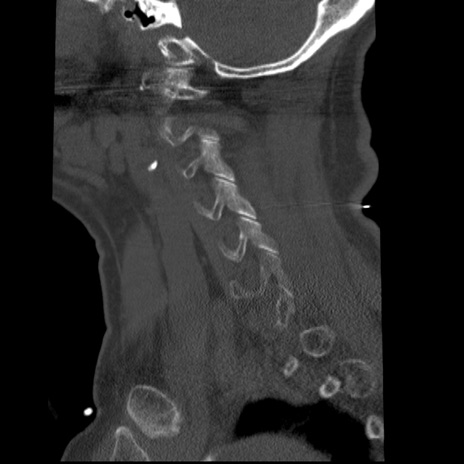

症例50 頚椎CT(矢状断像)

【症例】60歳代女性

【主訴】後頭部〜右後頸部にかけての痛み

【現病歴】本日飲食店でコーヒーを飲んでいたところ、突然後頭部〜右後頸部にかけて痛みが出現し、右上肢の感覚障害を伴ったため救急要請。

【身体所見】脳神経学的に明らかな異常所見を認めず。右上肢に軽度の感覚障害あり。

異常所見と診断は?

頚椎CT